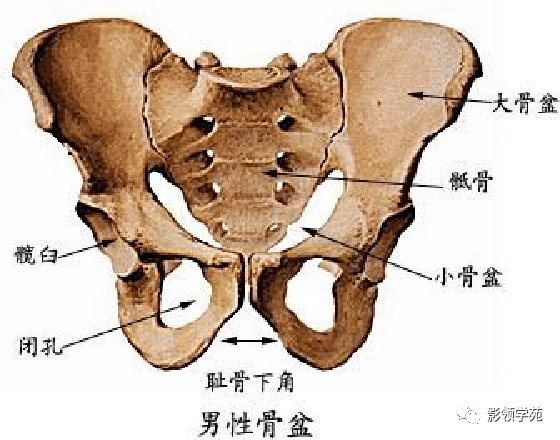

骨骼系统

骨骼系统